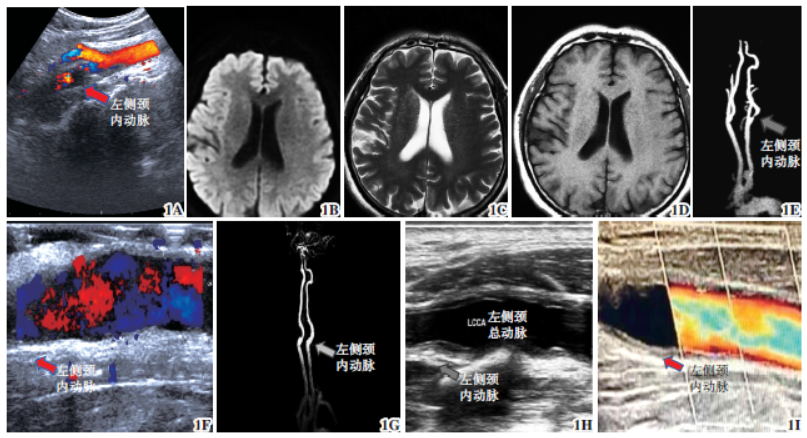

术前肝功能:谷丙转氨酶20U/L(参考值:5~40),谷草转氨酶18U/L(参考值:8~40)。术前彩超(图1A):左侧颈总动脉及颈内动脉起始部重度狭窄(70%~99%),流速330cm/s,斑块内可见溃疡形成;右侧颈总动脉及颈内动脉起始部中度狭窄,流速190cm/s。头部MRI(图1B~1D):未见明确梗死灶。颈部MRA(图1E):左侧颈内动脉起始部管腔重度狭窄,右侧椎动脉重度狭窄至闭塞。

术中超声探查(图1F):左侧颈总动脉、颈内动脉血流通畅。皮下留置引流管1 根,接负压吸引瓶,逐层缝合颈阔肌、皮下及皮肤。包扎伤口,术毕。术中出血50ml,麻醉清醒后拔除气管插管返回普通病房。术后当天意识清楚,生命体征平稳。1.3 术后复查及随访术后复查颈动脉MRA(图1G):左侧颈总动脉、颈内动脉血流通畅。术后病理提示:颈动脉粥样硬化性斑块。术后肝功能结果:谷丙转氨酶23U/L,谷草转氨酶22U/L。住院10d 后病情好转,步行出院。出院后6 个月(图1H)、4 年(图1I)门诊随访,颈动脉狭窄未复发。

图1 肝移植术后无症状重度颈动脉狭窄1A 术前颈动脉彩超提示左侧颈内动脉重度狭窄1B~1D 术前MRI 序列(DWI 序列、T1序列、T2flair 序列)未见新发梗死及出血灶1E 术前颈动脉MRA提示左侧颈内动脉重度狭窄1F 术中彩超1G 术后复查颈动脉MRA,左侧颈内动脉斑块剥脱后,血流通畅1H 术后6 个月门诊复查颈动脉彩超提示血流通畅1I 术后4 年门诊复查颈动脉彩超提示血流通畅